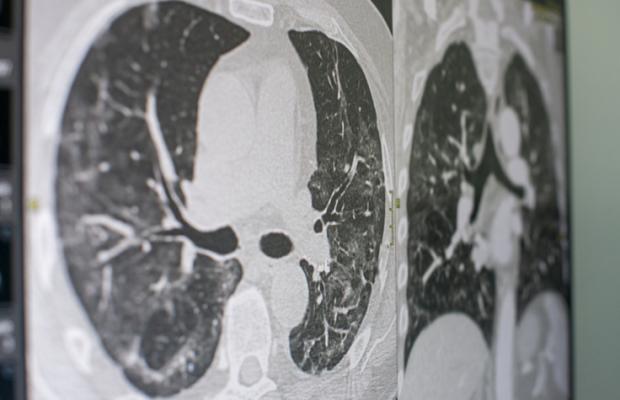

December 22, 2023 — Annual low-dose CT screening has been recently shown to result in high cure rates of over 80%, but methods of conducting a lung cancer screening program vary and best practices have yet to emerge. To address this, the International Association for the Study of Lung Cancer (IASLC) Early Detection and Screening Committee published a perspective that contains considerations for screening program managers to follow. The study is published in the Journal of Thoracic Oncology, the official journal of the IASLC and is available here: https://www.jto.org/article/S1556-0864(23)02369-9/fulltext.

The report illustrates one important aspect of a lung cancer screening program—timing between screenings. The benefit of LDCT screening depends on detection of small, early lung cancers when they are curable. Increasing the time between screenings leads to larger and later stage tumors as demonstrated by the NELSON results of annual screening compared with longer intervals of two-year and two-and-a-half years.

This report identifies the key components of the regimen of LDCT screening for lung cancer which include the need for a management system to provide data for continuous updating of the regimen and provides quality assurance assessment of actual screenings. Multi-disciplinary clinical management is needed to maximize the benefit of early detection, diagnosis, and treatment of lung cancer. Different regimens have been evolving throughout the world as the resources and needs may be different for countries with limited resources.